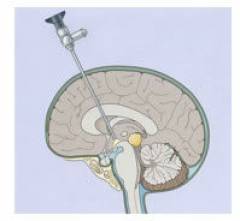

Проводят экстренную операцию:

- Ребенку дают наркоз.

- В черепе проделывают отверстие. Если швы и роднички еще не заросли, то можно сделать прокол. У детей старшего возраста используются фрезы.

- В желудочек мозга проводят силиконовый катетер и погружают его на необходимую глубину. При некоторых пороках развития приходится сверлить два отверстия и устанавливать два катетера в оба желудочка – в правый и левый.

- Другой конец катетера соединяют со специальной емкостью.

Эта мера является временной. Во время ухода за прооперированным ребенком необходимо строго соблюдать правила асептики, чтобы не занести инфекцию. Емкость, в которую оттекает спинномозговая жидкость, периодически меняют.